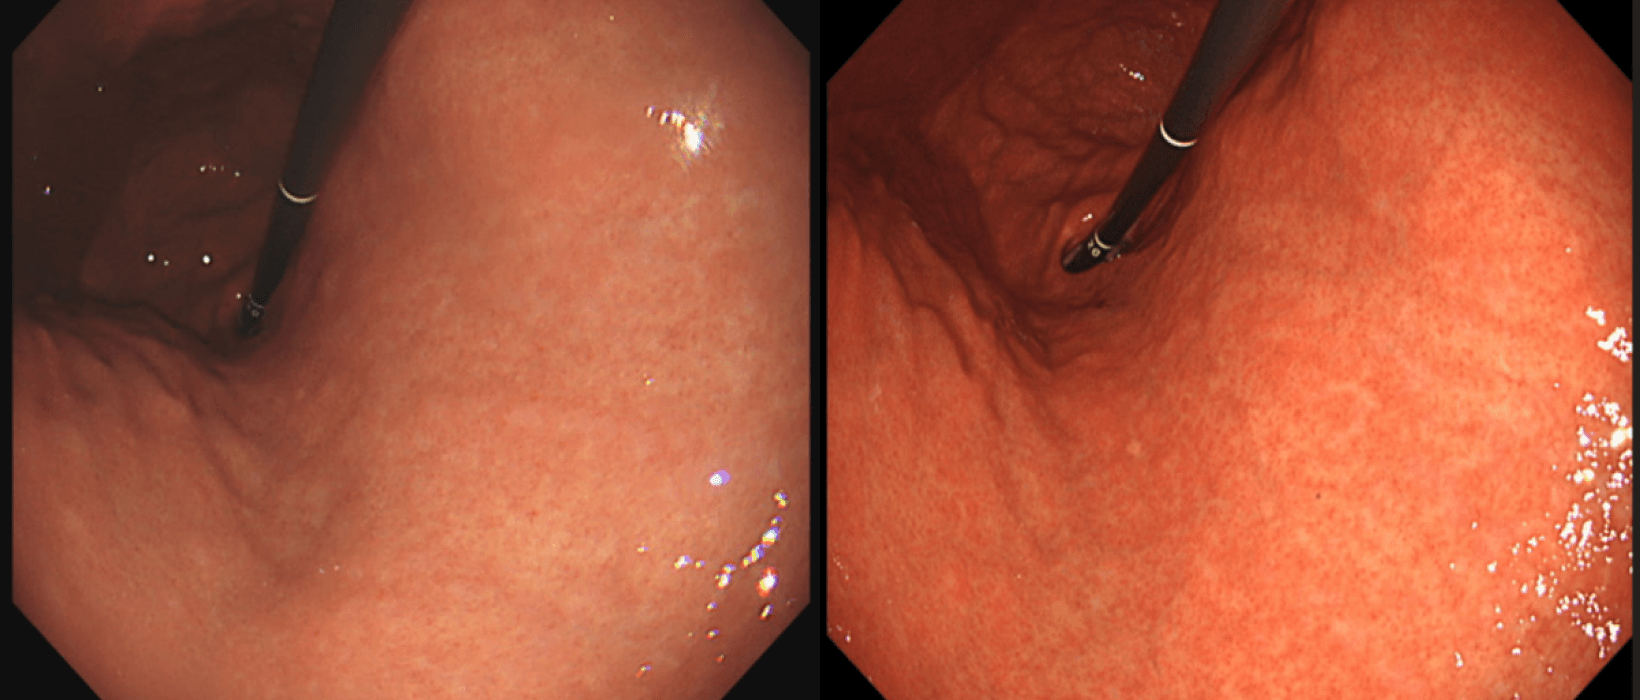

上記写真は同一患者さんに対し、左がオリンパス社Q260、中央がQ290、右が1500というカメラでとったものです。右にいくほど胃の微細構造がくっきりしていくのがおわかりいだだけると思います。